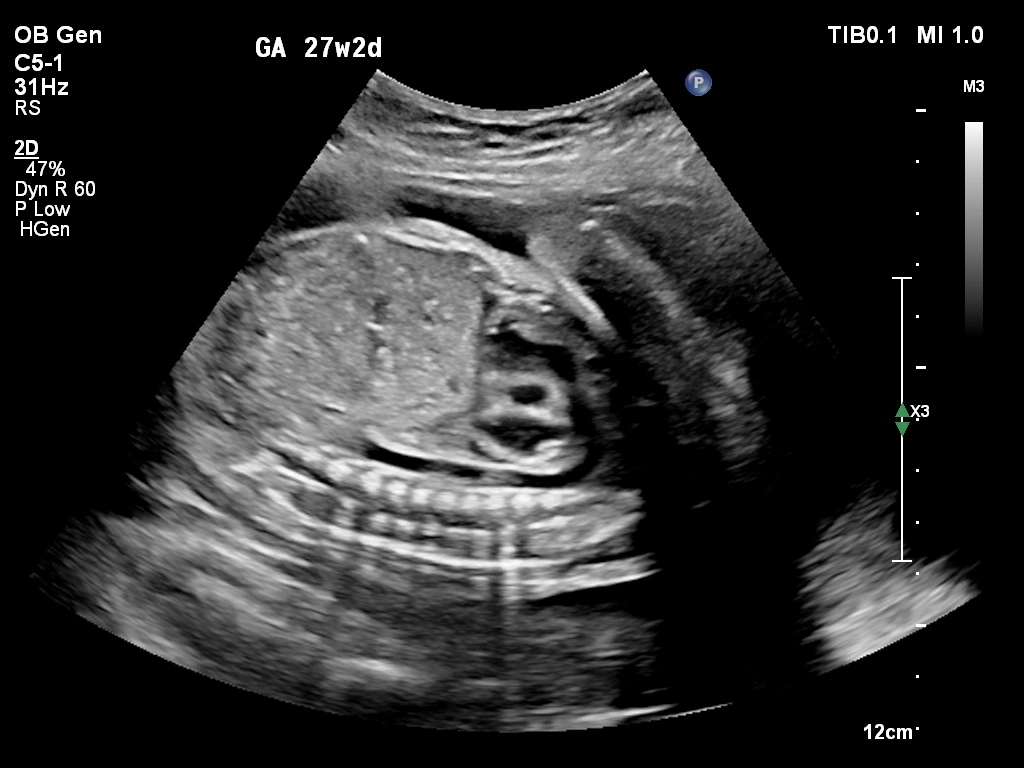

🔹 Anomaly Scan (Level II Ultrasound)

Anomaly Scan is a detailed ultrasound performed during pregnancy (usually between 18 and 22 weeks) to check the baby’s development. It helps detect structural abnormalities in the brain, heart, spine, kidneys, and other organs. This scan ensures your baby is growing normally and helps doctors identify any potential complications early. If you are looking for a reliable anomaly scan in Kathmandu, an early and accurate diagnosis is essential for a safe pregnancy.